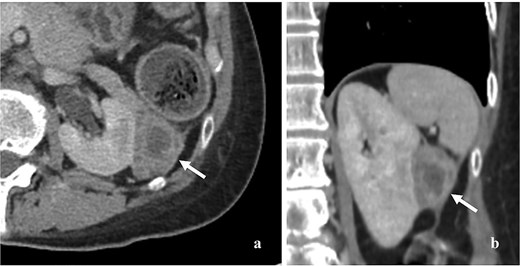

A 59-year-old woman presented with a pancreatic tail mass, incidentally detected during a follow-up computed tomography (CT) scan for colon cancer surveillance. Approximately four years earlier, she had been diagnosed with stage III colon cancer according to the American Joint Committee on Cancer (AJCC) eighth edition. She completed adjuvant chemotherapy, and subsequent surveillance showed no evidence of disease. Three years later, she presented with postmenopausal bleeding. A pathological analysis from fractional curettage confirmed NECC. Further metastatic evaluation, including whole-abdomen and chest CT scans, revealed no evidence of distant organ metastasis. She subsequently underwent concurrent chemoradiation therapy (CCRT) as curative treatment for NECC. During the course of CCRT, after approximately three cycles, the previously mentioned pancreatic tail mass was detected. A contrast-enhanced CT scan of the whole abdomen revealed a 4.5 × 4 cm heterogeneous, minimally enhancing mass in the pancreatic tail region with no evidence of pancreatic and renal invasion (Fig. 1). There was no pancreatic duct dilation, lymphadenopathy, or distant organ metastasis. However, the NECC appeared to be responding to CCRT, as the mass had decreased in size compared to previous imaging.

Contrast enhancing CT scan of whole abdomen showed 4.5 × 4 cm heterogeneous and minimal enhancing mass (arrow). (a) Axial section, (b) coronal section.